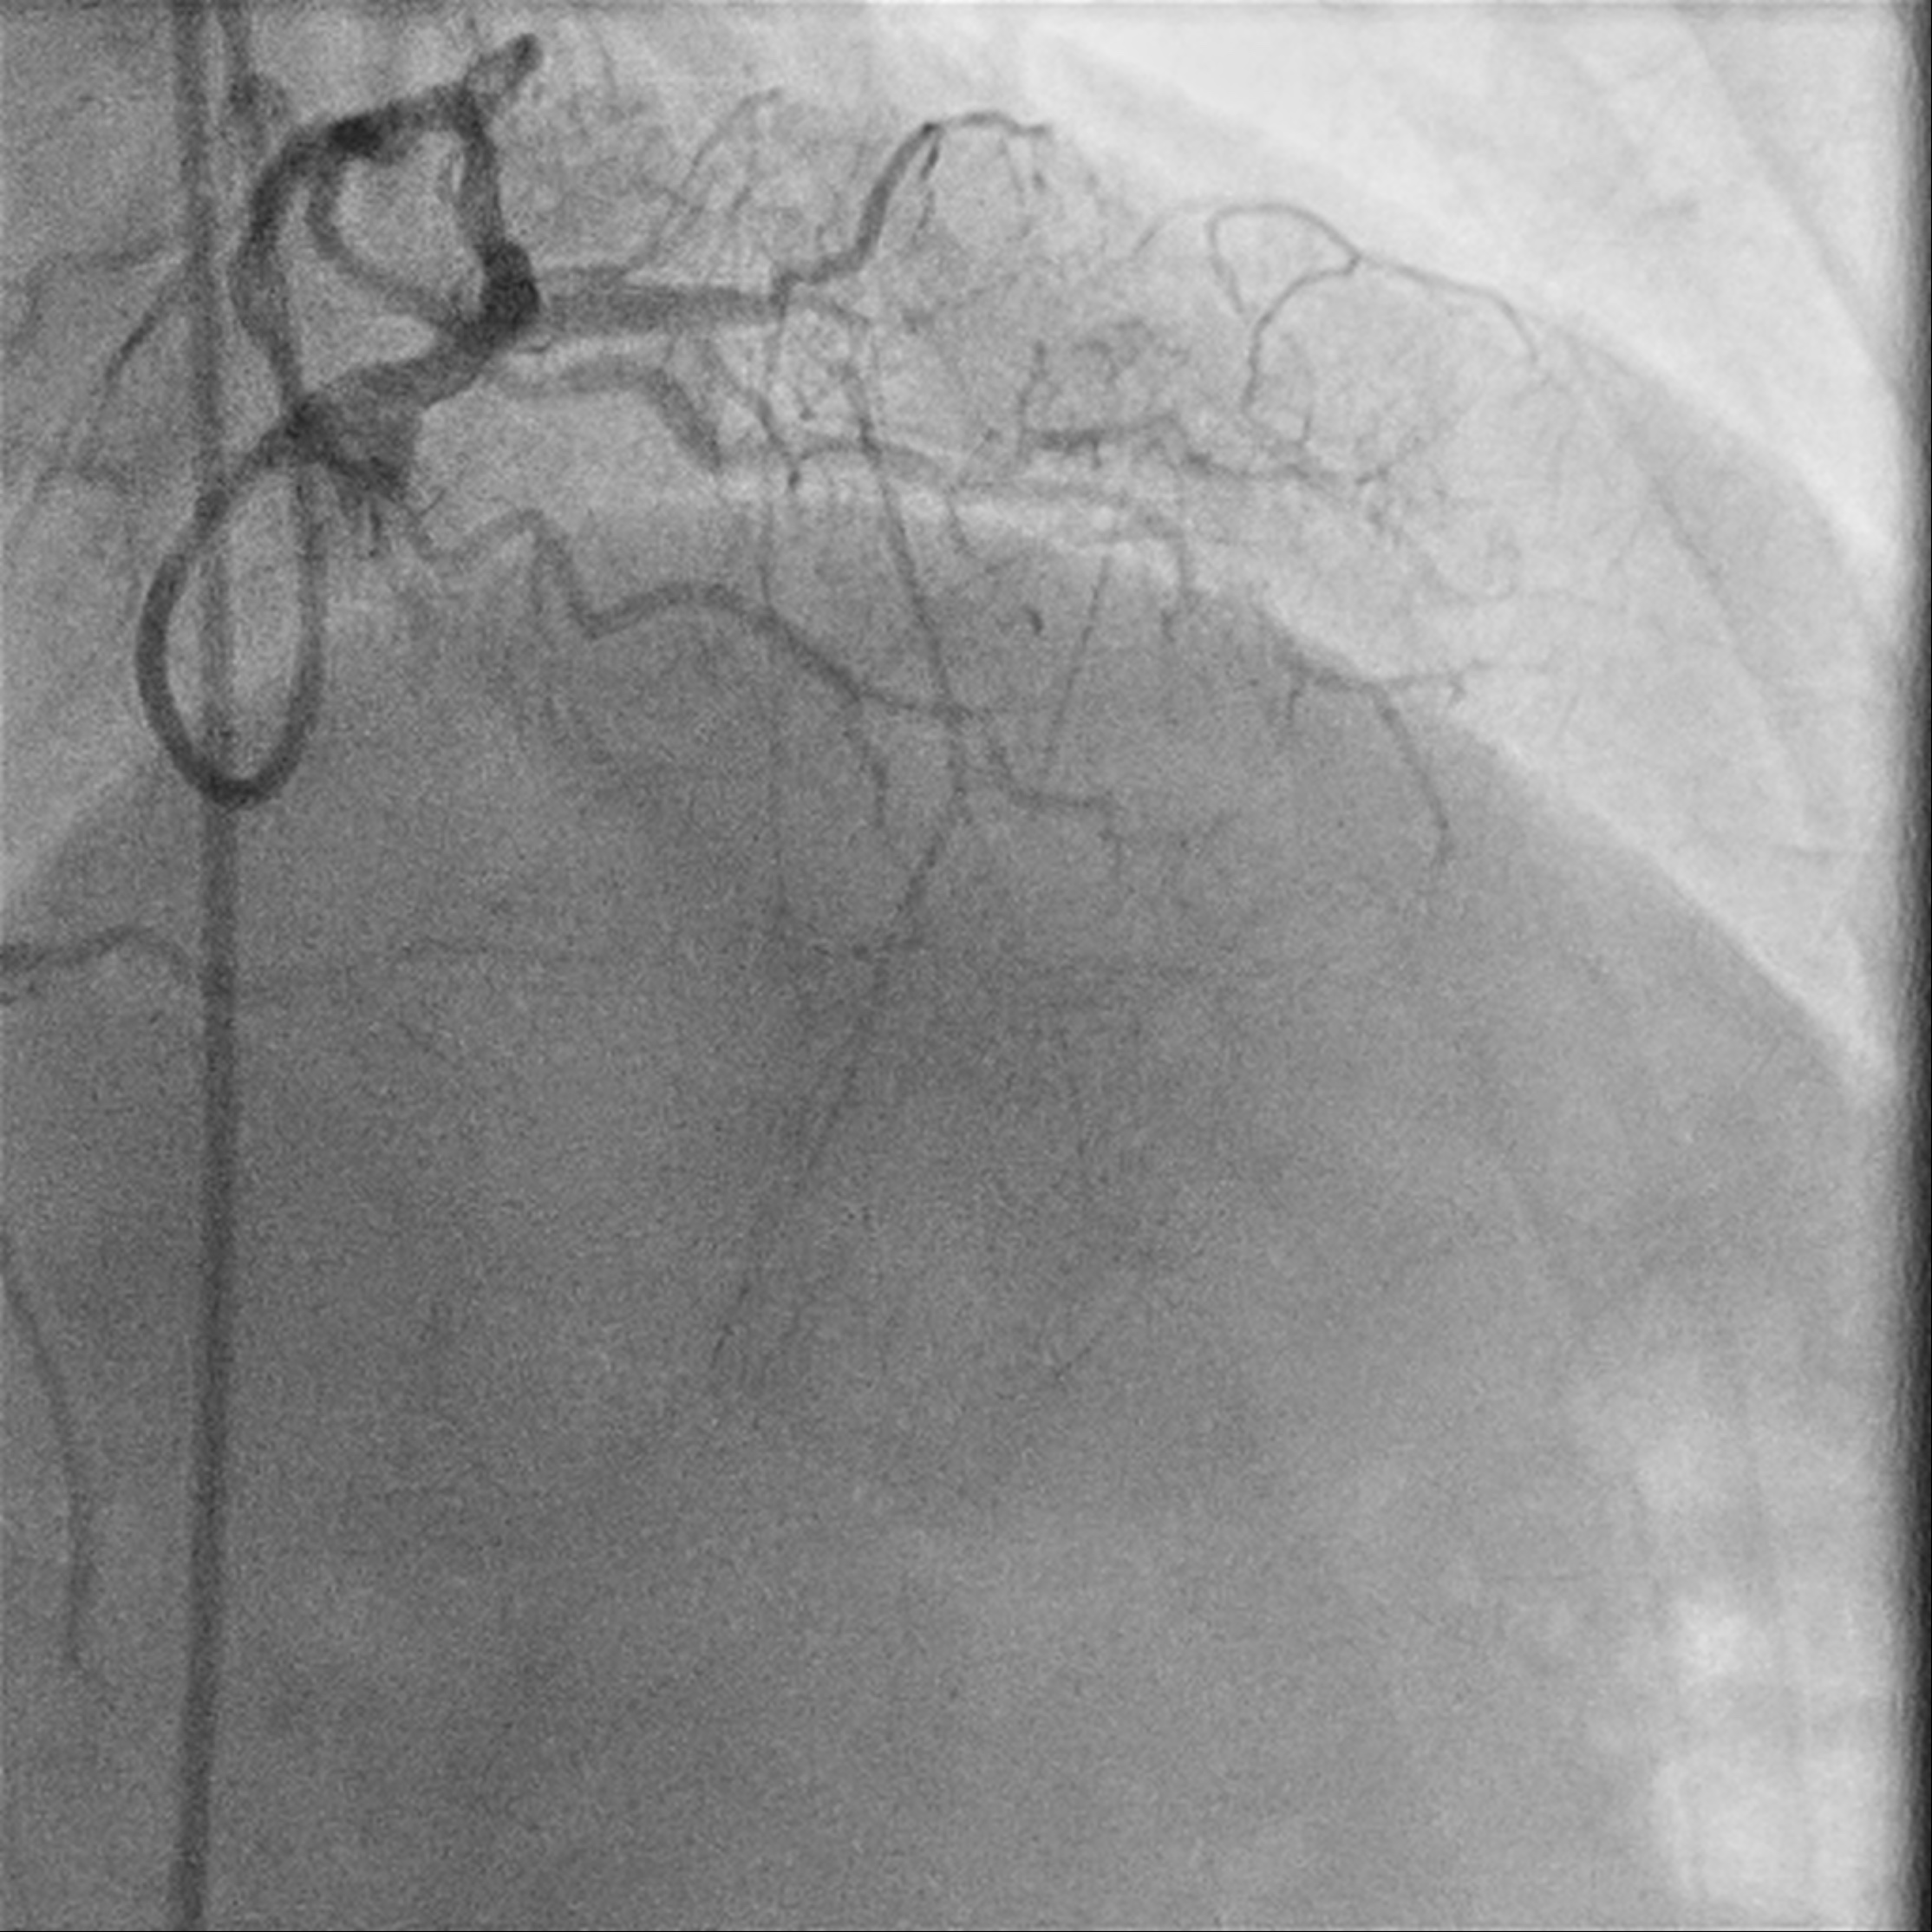

A 49-year-old male who is a chronic smoker and ex-IV drug addict was presented as heart failure and NSTEMI. Severely impaired LV systolic function of 15%, global hypokinesia. Calcified coronary arteries with mRCA severe stenosis, mid to distal RCA critical lesion; retrograde flow from PL branch to mLAD. mLAD CTO with bridging collaterals. LCX diffuse moderate stenosis, with collateral to PL branch. MRI heart confirms viable myocardial over LAD territory, CABG turned down.

Relevant Catheterization Findings